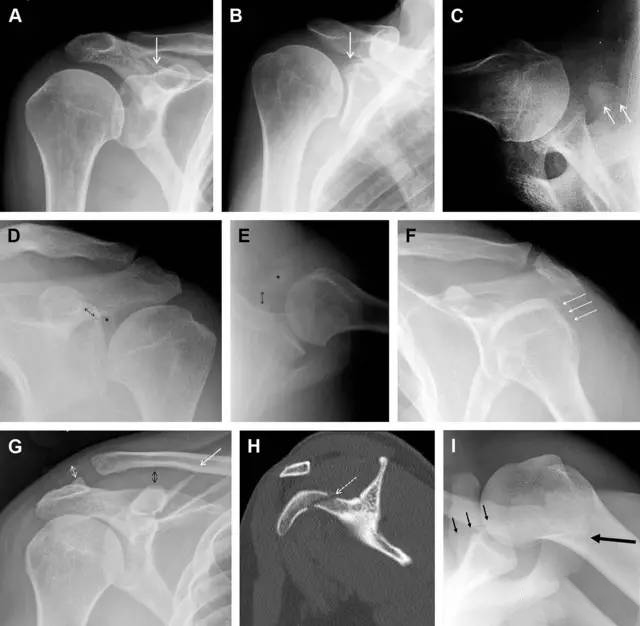

图4 喙突骨折。66 岁男性患者,猎枪射击后右肩前方疼痛。(A)内旋位前后位片投影隐约可见喙突基底部骨折(白色箭头),(B)外旋位前后位片投影结构存在重叠,(C)腋位投影时可良好显示。(D~F)喙突骨折伴 Hill-Sachs 损伤:肩关节脱位后慢性疼痛,喙突骨折块(*)向前外侧移位(双箭头),在外旋前后位(D)及腋位(E)片上均可显示,在内旋位前后位(F)片上,喙突被遮挡,但可见肱骨头 Hill-Sachs 损伤。(G、H)喙突骨折伴肩锁关节脱位,肩锁关节分离(白色双箭头),而喙锁间距正常(黑色的双箭头),应警惕喙突骨折。(I)喙突与肩峰骨化中心:对于未成年人,喙突与肩峰骨化中心可同时存在,易与骨折混淆,此时,拍对侧的 X 线片对比将有助于诊断。